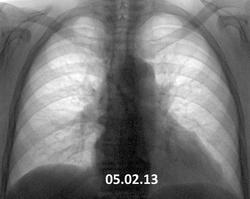

03.01.14 - острых жалоб нет, одышка. Летом лечила пневмонию. Предыдущая флгр. 05.02.13. Как относится к пневмотораксу справа - как к острому состоянию или, может,  как к состоянию после перенесенного пневмоторакса?

Как по мне - состояние острое...в прошлом году ничего подобного не было...анамнез с ПРИСТРАСТИЕМ!!!!!!!!!

А нужно ли нам (рентгенологам) относится к выявленному пневмотраксу с точки зрения остроты процесса (в данном случае)? Разве мы сможем утверждать, что ПТ не возник летом?

Повторил бы вдох+выдох, если недоступна скопия

я не понимаю почему легочный рисунок везде прослеживается..frown

Потому что ПТ ограниченый.

Виктор Григорьевич, это просто предыдущая архивная флгр.от 03.01.13, а пневмонию лечила летом. К сожалению - что за пневмония, и т.д.? - снимков нет.